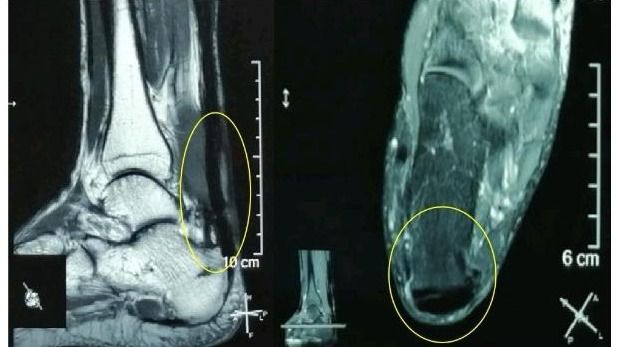

“感谢伍教授!我的跟腱疼痛、肿胀基本缓解了,踝关节活动也好多了,跑步也轻松了!”49岁的郑先生(化名)在电话中连声道谢。在跟腱断裂后,尽管做了修补术,但在半年多的时间里,他因跟腱疼痛、肿胀、踝关节活动受限而苦不堪言。幸好,在bat365在线中国登录入口孙逸仙纪念医院康复科副主任伍少玲教授的帮助下,他接受了“超声引导下...